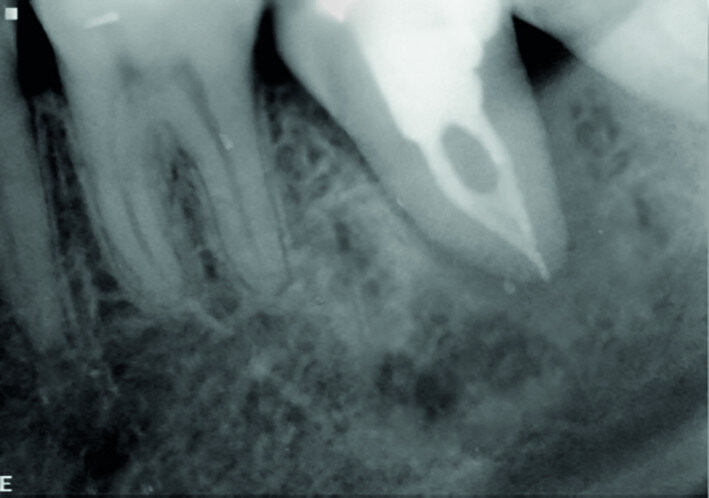

Fig. 15d: Radiograph: Twelve-year recall.

The left mandibular second molar of a 35-year-old female patient had been compromised because of a vertical root fracture and a large periapical lesion was present. After explanation and informed consent, the treatment was scheduled. The right mandibular third molar was preferred as a donor to the left mandibular third molar because of a more compatible anatomy and for an easier stabilisation. After local anaesthesia of both the donor and the recipient sites with 2 per cent mepivacaine with 1:100,000 adrenaline, the left mandibular second molar was extracted and the alveolus debrided. Then the donor tooth was atraumatically extracted, quickly repositioned in the recipient site and stabilised with sutures at about 1.5–2.0 mm of infraocclusion. An antibiotic (amoxicillin/clavulanic acid, 1 g, by mouth twice a day for five days) and a non-steroidal anti-inflammatory drug (ibuprofen, 600 mg, by mouth twice a day for five days) were prescribed, along with rinses with 0.2 per cent chlorhexidine. The sutures were removed after two weeks and endodontic treatment was performed after three months. The periapical lesion healed and the tooth was fully functional after 12 years (Figs. 14a–d & 15a–d).